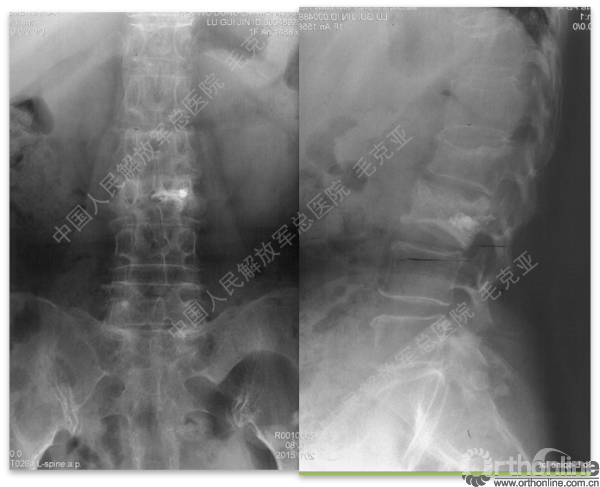

导语:随着社会老龄化的不断加速,骨质疏松性椎体压缩骨折作为一种普遍存在的老年骨科疾病已经成为现今骨科界的一个热点话题。传统的保守疗法治疗效果不佳,而现有的椎体增强技术又具有多种风险和缺陷。针对这种现状,中国人民解放军总医院毛克亚教授提供了一种新的解决方法。